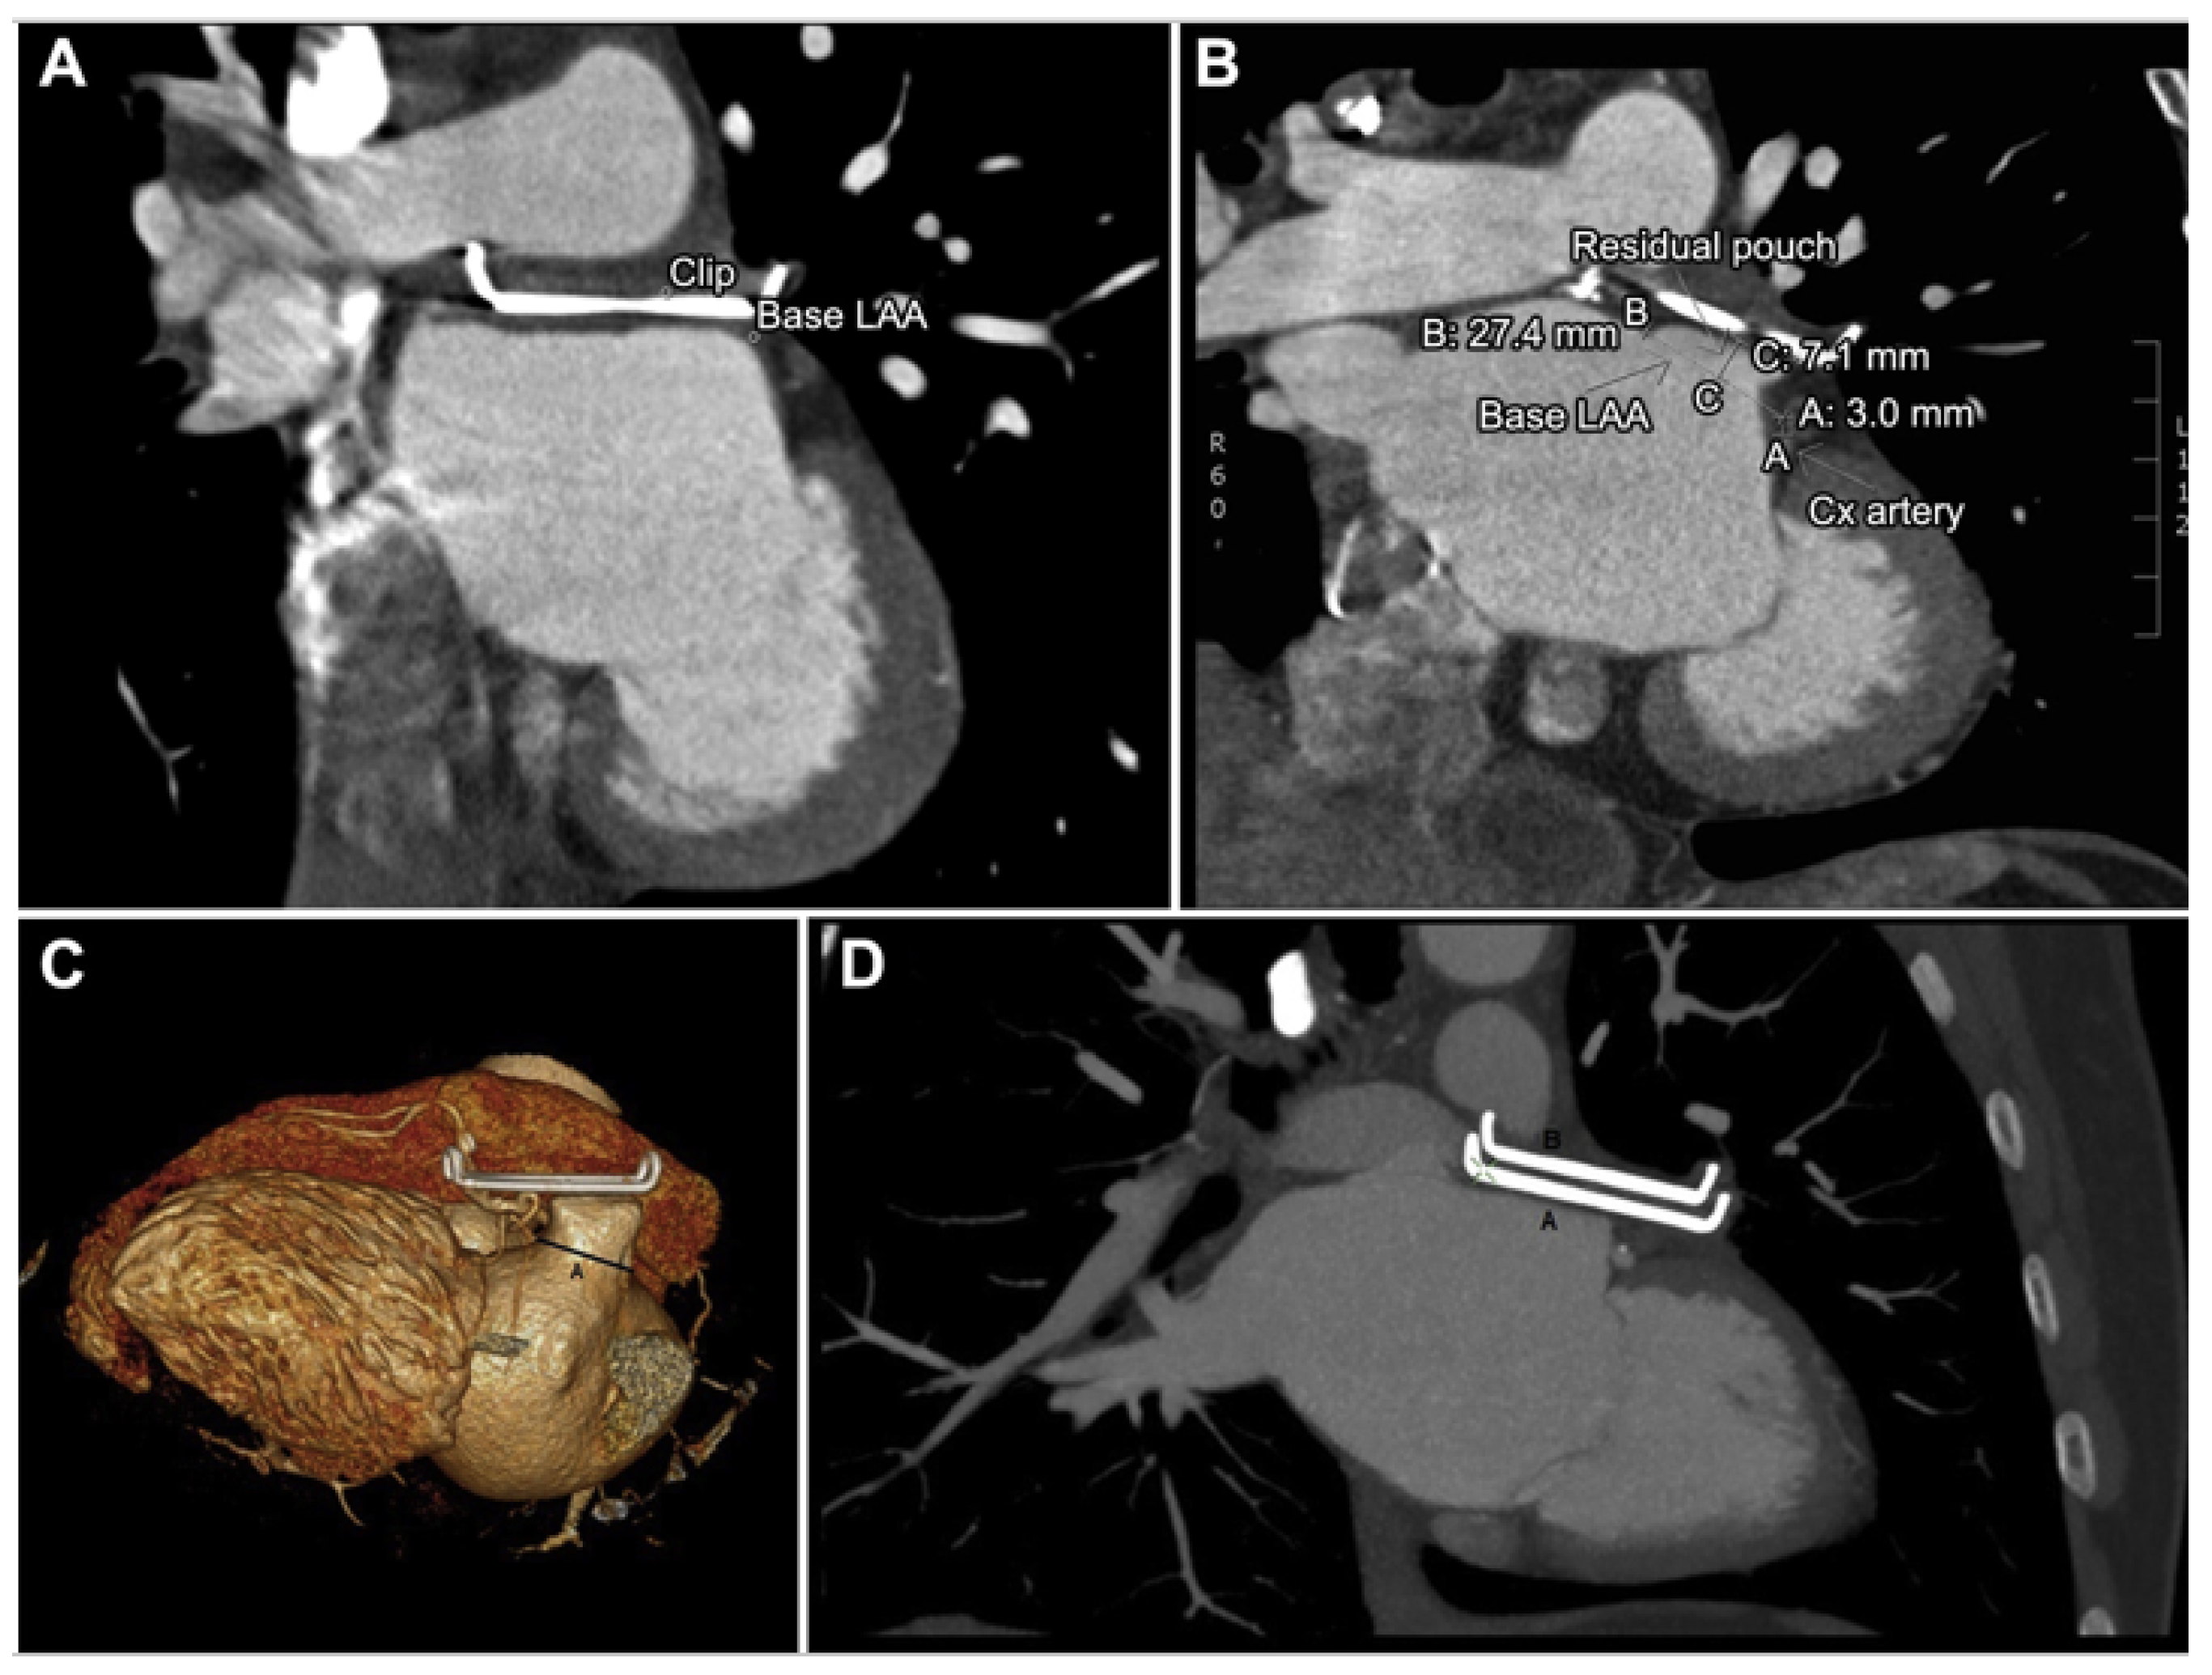

3.5. Epicardial Devices

4. Conclusions and Future Directions